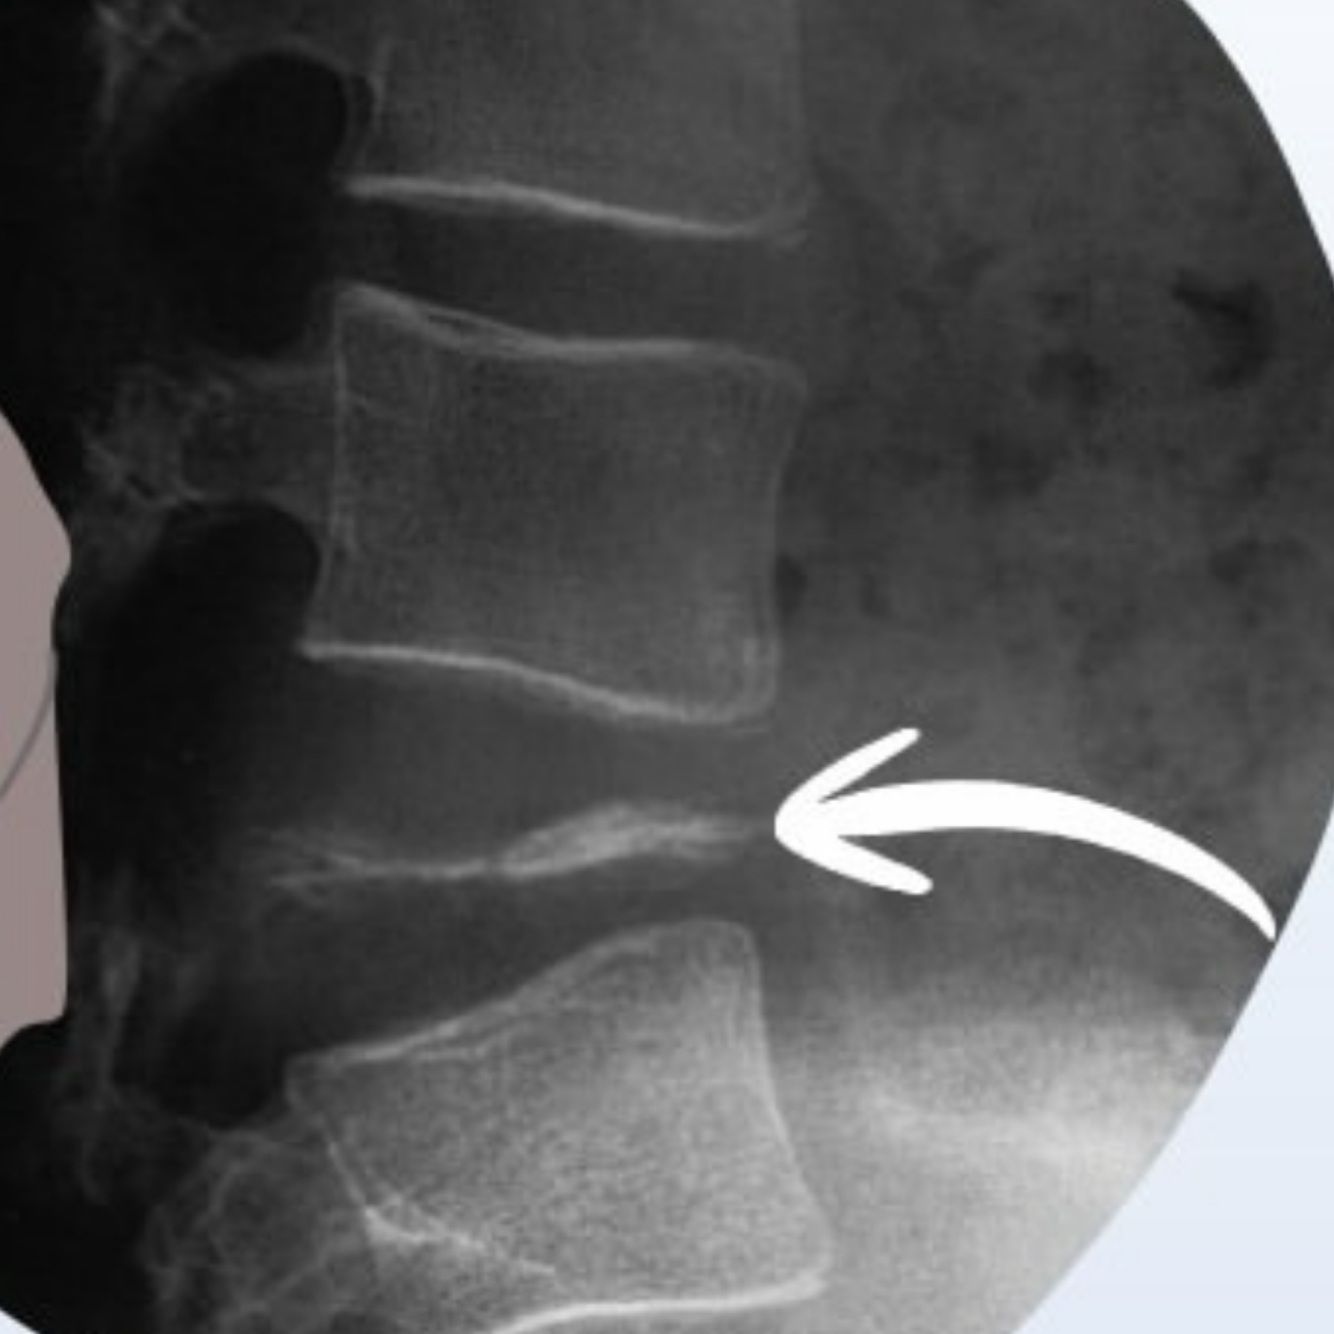

Qual alteração apresentada?

(Entesófito ou osteófito)

A

Entesófito

• O Entesófito tende a ser vertical, no eixo do ligamento

• os discos estão normais